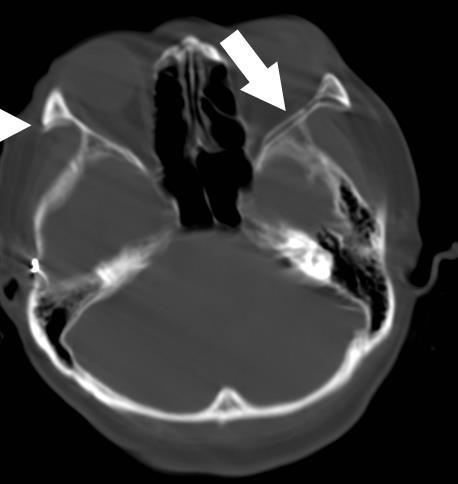

Cristina Felice Civitillo (1), Frédéric Jonathan Leis (2), Céline Habre (3), Francisca Barcos- Munoz (1) (1) Néonatologie et soins intensifs pédiatriques, Département Femme Enfant et Adolescent, HUG, Hôpitaux Universitaires de Genève (2) Atelier 3Durable, Université de Genève (3) Département de Diagnostic, Service de Radiologie, HUG, Hôpitaux Universitaires de Genève

IRM de vrais patients → Voies aériennes (bouche-trachée)

Différents âges gestationnels (24 - 44 SA) et différents poids (400g - 4kg)

Impression 3D multi-matériel

Création simulateur haute fidélité pour intubation